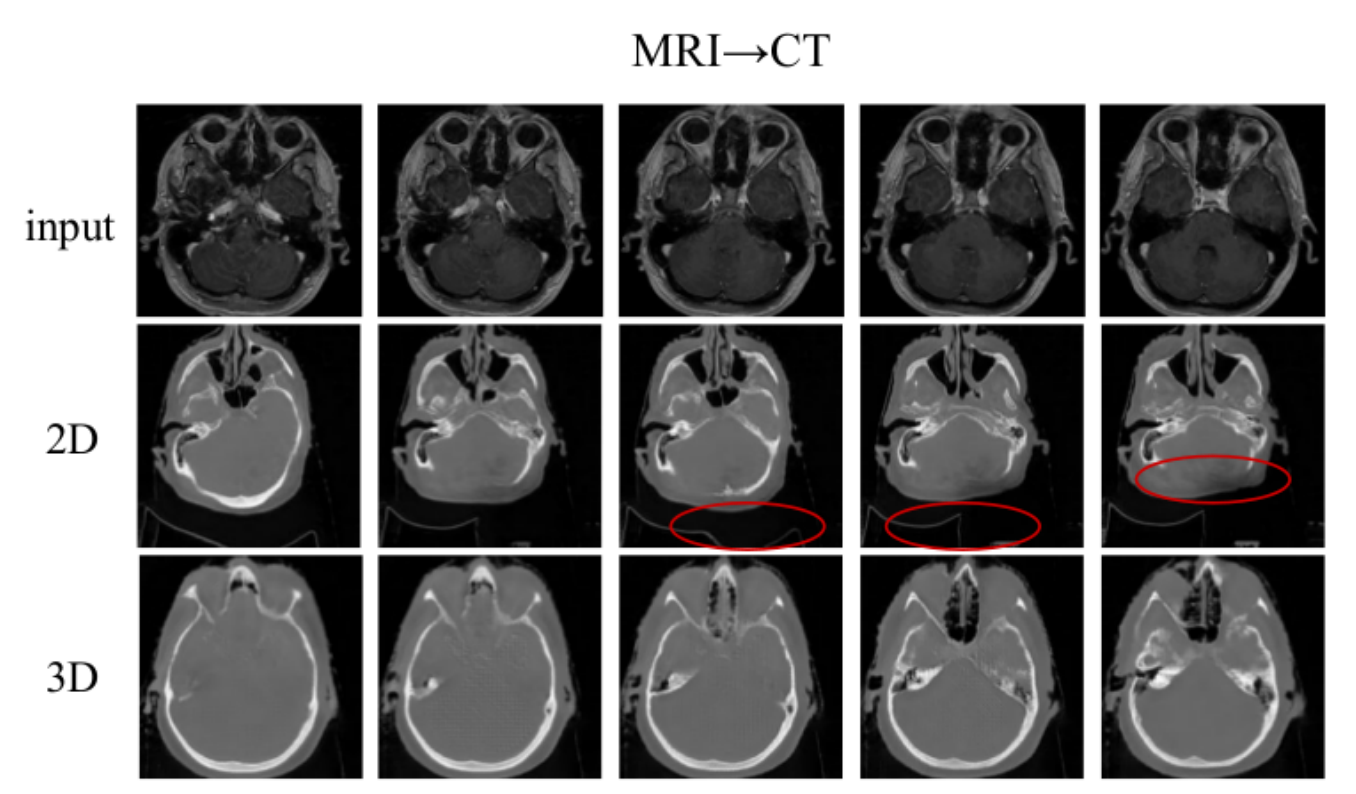

RIFT: Disentangled unsupervised image translation via restricted information flow

Ben Usman, Dina Bashkirova, Kate Saenko

[WACV 2023]: In this paper, we show that many state-of-the-art architectures implicitly treat textures and colors as always being domain-specific, and thus fail when they are not. We propose a new method called RIFT that does not rely on such inductive architectural biases and instead infers which attributes are domainspecific vs shared directly from data. As a result, RIFT achieves consistently high cross-domain manipulation accuracy across multiple datasets spanning a wide variety of domain-specific and shared factors of variation.